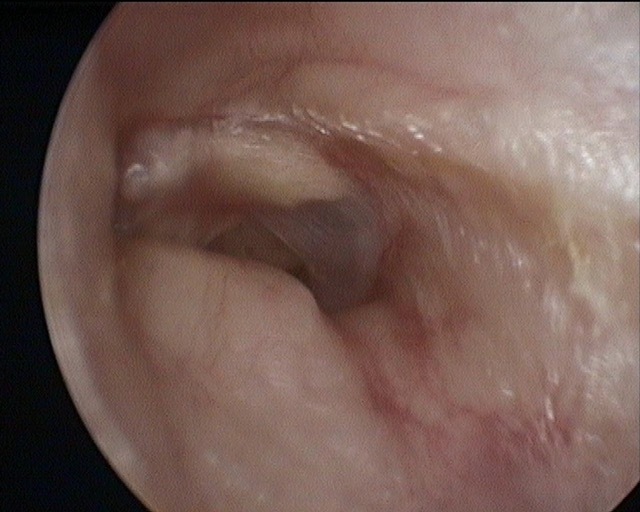

Atelectasis/Retraction